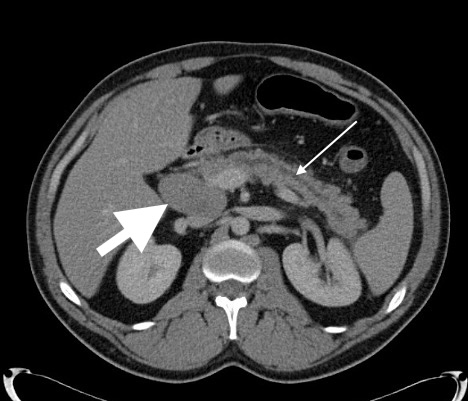

Case Presentation: A 29-year-old male with no medical history presented with abdominal pain and diarrhea after a trip to Key West. He described 2 days of constant epigastric pressure and cramping with no relation to food intake or bowel movements, along with 1 night of black, watery diarrhea. He denied fever, weight loss, night sweats, or easy bleeding/bruising. He endorsed daily binge drinking while traveling, with no consumption of raw shellfish, illicit drug use, or unprotected sexual encounters. He lived in rural North Carolina and owned dogs, chickens, and cats. He had a 5 pack year smoking history and used no medications. Family history was significant for a “lymph node cancer” in his father. At presentation, vital signs were T 37.1°C, HR 96 bpm, BP 185/100 mmHg, RR 18, and SpO2 96% on room air. Exam showed epigastric tenderness with no cervical lymphadenopathy or jaundice. Laboratory results showed WBC 11.7 x10*9/L (H), Hgb 12.7 g/dL, Platelets 371 x10*9/L, absolute neutrophil count 9.2 x10*9/L (H), and absolute lymphocyte count normal. Elevated studies included fibrinogen 585 mg/dL, lipase 1,100 U/L, CRP 30 mg/L, and ESR 30 mm/h. Notably normal studies included a complete metabolic panel, lactate, APTT, PT, INR, GI stool pathogen panel, C. difficile assay, and ova/parasite exam. Peripheral smear showed a mild normocytic anemia. CT abdomen/pelvis showed acute interstitial pancreatitis, dilation of the main pancreatic duct, and multistation adenopathy throughout the abdomen and pelvis. A magnetic resonance cholangiopancreatography (MRCP) showed multifocal abnormal soft tissue deposits within the pancreas obstructing the main pancreatic duct. Both studies suggested a concern for lymphoma. Malignant hematology was initially unimpressed with his case due to the near normal CBC and normal LDH and uric acid. As such, an infectious workup for diffuse lymphadenopathy was pursued and negative for HIV, syphilis, tuberculosis, tick-borne illnesses, bartonellosis, and toxoplasmosis. He underwent EUS/ERCP with main pancreatic duct stenting and biopsy. Pathology ultimately resulted as diffuse large B-cell lymphoma.